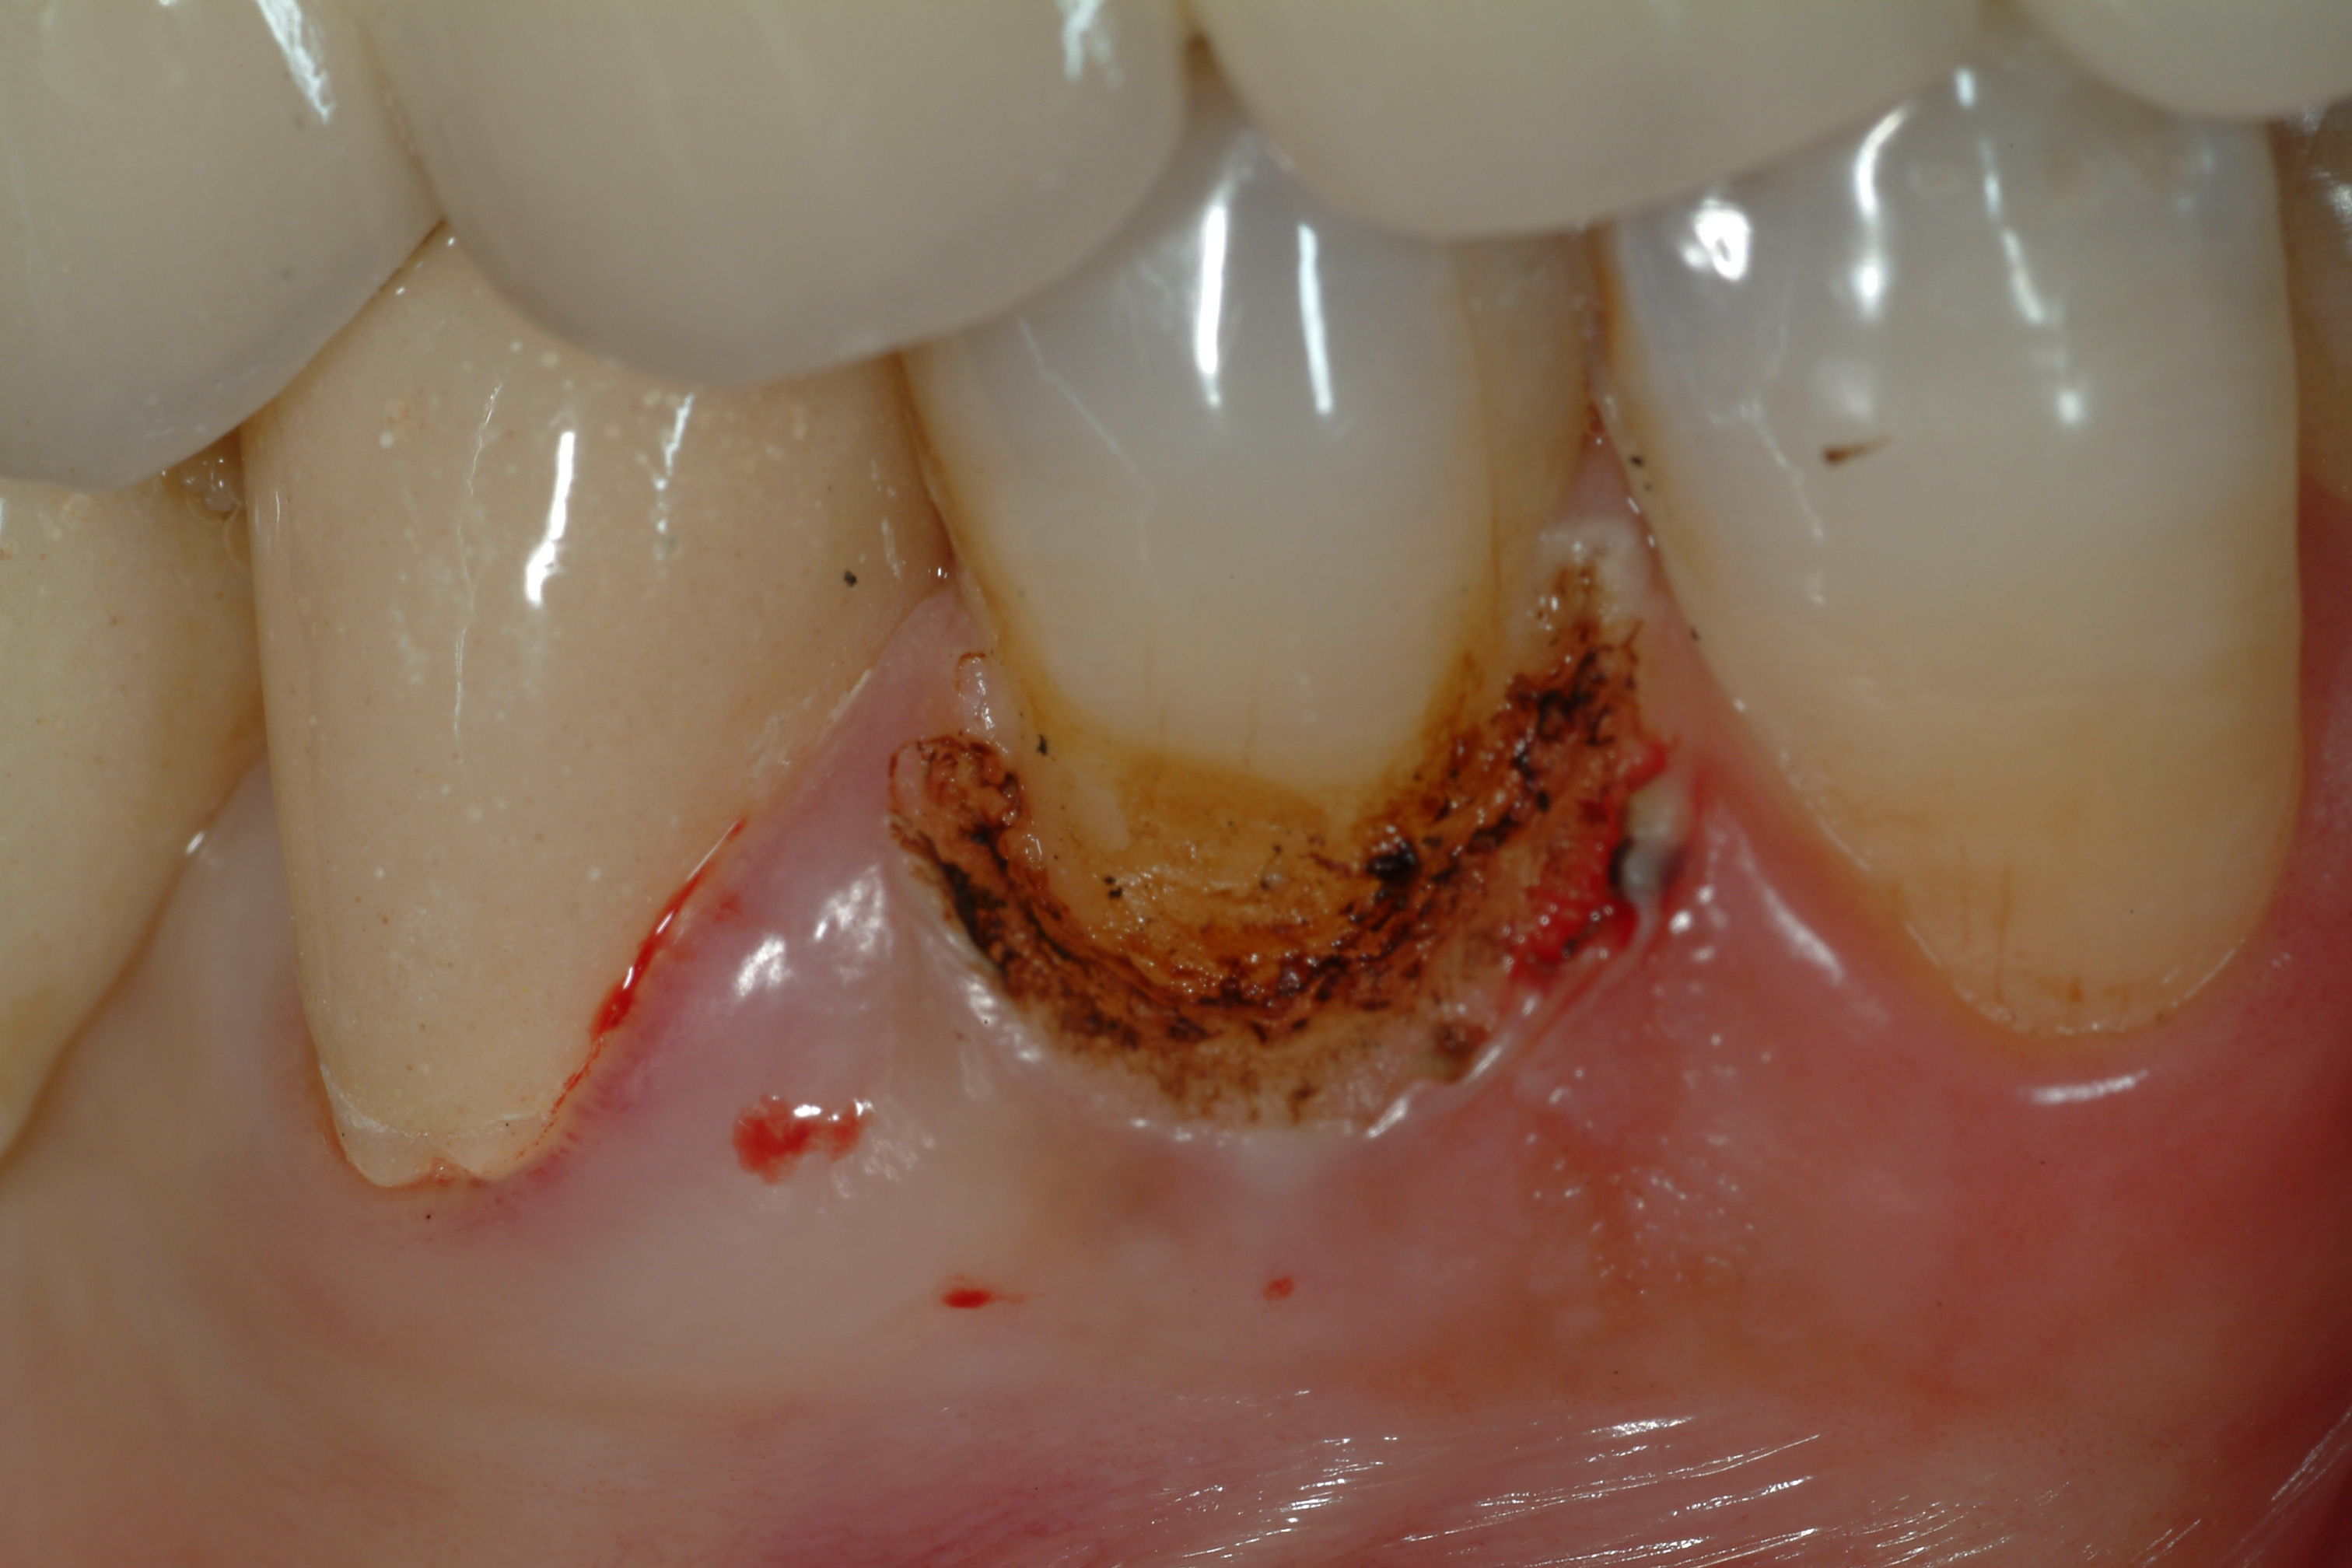

Lesione di classe V coronoradicolare trattate con laser e materiali compositi: una buona rifinitura e lucidatura dei margini dei restauri favorisce la salute parodontale.

Attraverso il laser è stato rimosso il tessuto parodontale che ricopriva buona parte del coletto e del versante coronale permettendoci di lavorare in completa assenza di sangue.